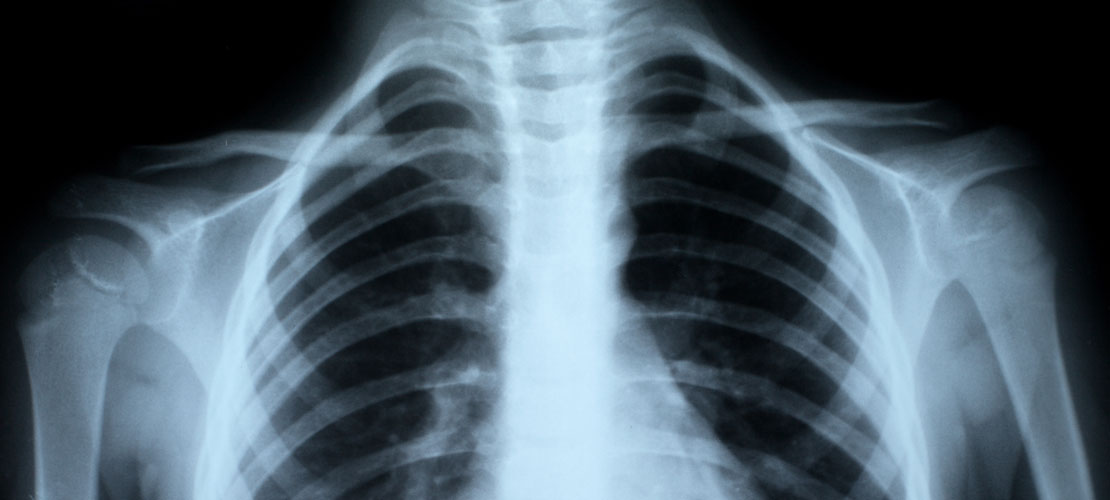

Spirometry (lung function test)

TB screenings and awareness campaigns